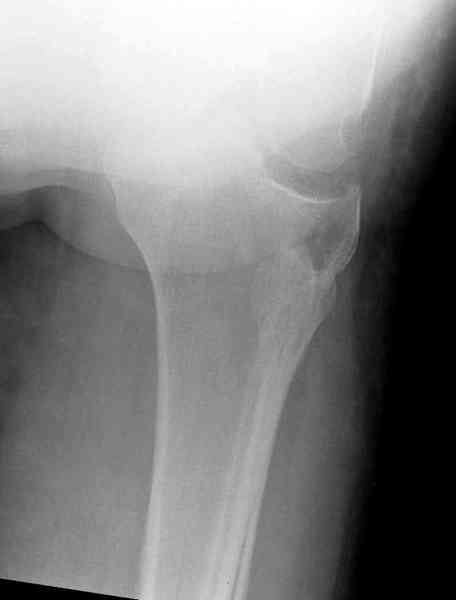

Это техника применяется, когда имеется

центральная импрессия, а при ипрессии с краевым переломом - после приподнимания импрессии опорная (Butress) пластина, как на снимке.